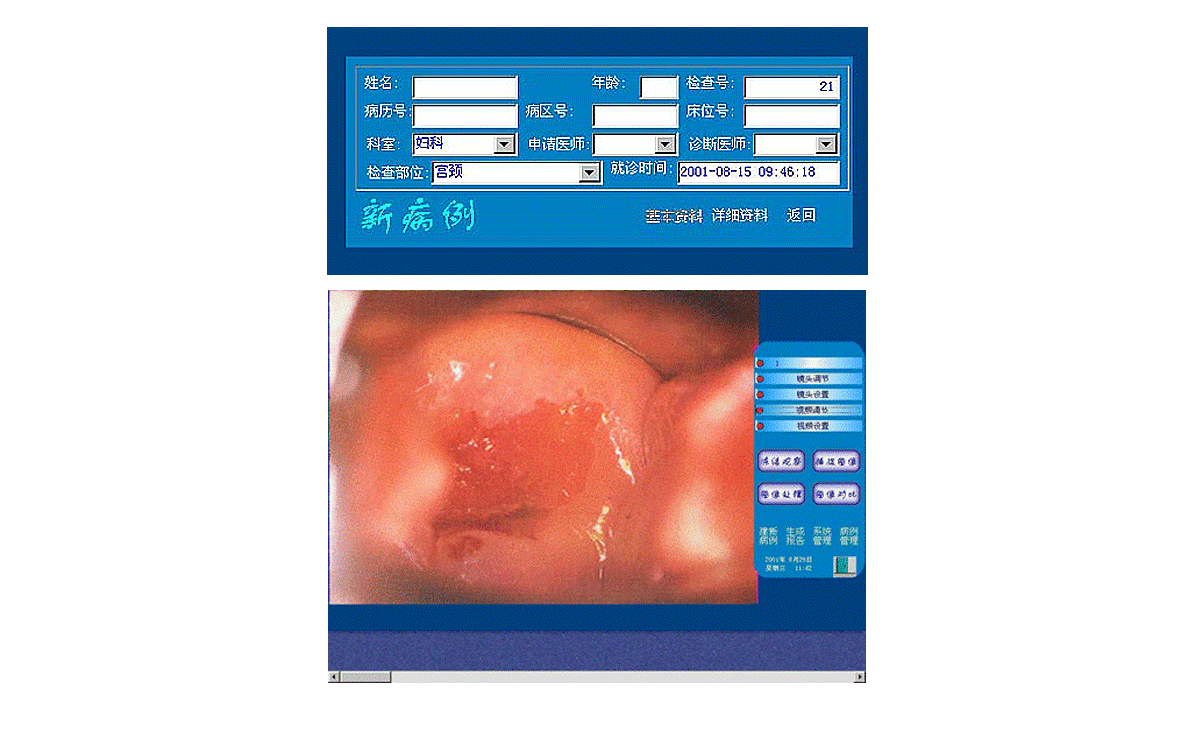

3、打開顯視器電源開關(guān),開啟主機(jī)電源總開關(guān),開啟陰道鏡系統(tǒng),待系統(tǒng)進(jìn)入正常窗口界面后,先創(chuàng)建新病例,通過觀察、采集、生成報(bào)告后,即可完成整個(gè)陰道鏡檢查與診斷操作。

2、用鼠標(biāo)點(diǎn)擊主界面窗口中<建新病例>按鈕后輸入病人的一些資料,再點(diǎn)擊該窗口上的<返回>按鈕,系統(tǒng)進(jìn)入圖像采集窗口界面,這時(shí)圖像采集窗口將顯示陰道鏡所觀察到的動態(tài)影像。